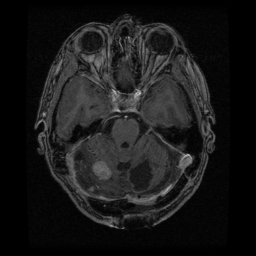

![]() |

| (a) | (b) | (c) | (d) |

Unsupervised Categorization: Our category discovery clusters are generally visually coherent within the cluster and size-balanced across clusters. However, image clusters formed only based on text information (of radiology reports) are highly unbalanced [49], with three clusters inhabiting the majority of images. Note that our method imposes no explicit constraint on the number of instances per cluster. Fig. 6 shows sample images and their top-10 associated key words from two randomly selected clusters (more results are provided in the supplementary material). The LDPO clusters are found to be clinically or semantically related to the corresponding key words, which describe presented anatomies, pathologies (e.g., adenopathy, mass), their associated attributes (e.g., bulky, frontal) and imaging protocols or properties.

The category discovery clusters employing our LDPO method are found to be more visually coherent and cluster-wise balanced in comparison to the results in [49] where clusters are formed only from text information ( radiology reports). Fig. 7 Left shows the image numbers for each cluster from the AlexNet-FC7-Topic setting. The numbers are uniformly distributed with a mean of 778 and standard deviation of 52. Fig. 7 Right illustrates the relation of clustering results derived from image cues or text reports [49]. Note that there is no instance-balance-per-cluster constraints in the LDPO clustering. The clusters in [49] are highly uneven: 3 clusters inhabit the majority of images. Fig. 6 shows sample images and top-10 associated key words from 5 randomly selected clusters (more results in the supplementary material). The LDPO clusters are found to be semantically or clinically related to the corresponding key words, containing the information of (likely appeared) anatomies, pathologies (e.g., adenopathy, mass), their attributes (e.g., bulky, frontal) and imaging protocols or properties.